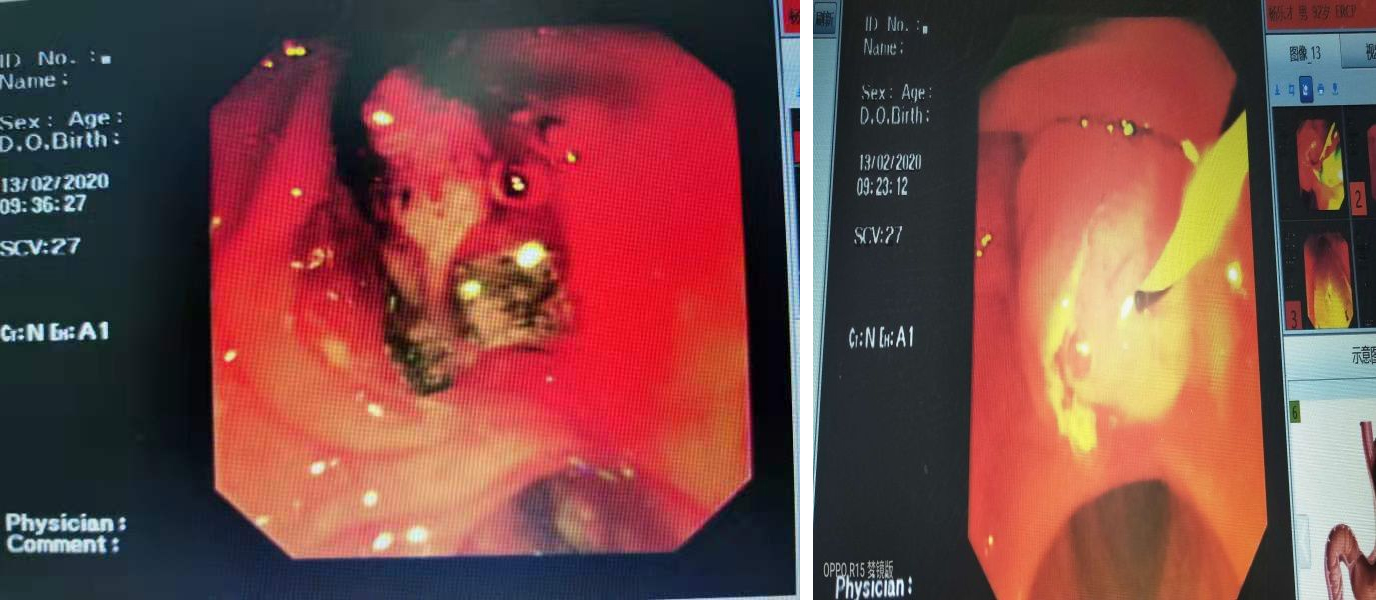

患者高齡,同時患有膽囊結(jié)石及2型糖尿病,入院時已存在寒戰(zhàn)高熱及梗阻性黃疸,如不及時處理,很可能出現(xiàn)感染性休克導(dǎo)致多臟器功能衰竭?紤]到患者平素常年臥床,心肺功能減退,外科手術(shù)風(fēng)險很高,且創(chuàng)傷大,反復(fù)和家屬溝通病情,家屬決定先入該院科行ERCP。入住消化科后經(jīng)討論并充分評估病情,決定盡快行ERCP,創(chuàng)傷小,風(fēng)險小,患者獲益最大。在韓新臣主任醫(yī)師的指導(dǎo)下,陳新孚副主任醫(yī)師在消化內(nèi)鏡中心護士戴文帝默契配合下用時40分鐘成功取出患者膽總管內(nèi)多枚結(jié)石,最大結(jié)石直徑10mm,另外術(shù)中發(fā)現(xiàn)膽道內(nèi)大量膿液,提示其合并化膿性膽管炎。如果確診再晚一點,不及時行ERCP取石,患者隨時都有感染性休克可能,后果不堪設(shè)想。術(shù)后患者68歲的兒子激動的握住韓新臣主任醫(yī)師、陳新孚副主任醫(yī)師的雙手說:“您們真是妙手回春,華佗在世啊!!!”。術(shù)后患者未再出現(xiàn)發(fā)熱,也未出現(xiàn)出血穿孔及胰腺炎等并發(fā)癥;颊吆芸炜祻(fù)出院。在辦理出院的時候,老爺子像個孩子一樣開心的說:“別人感冒還要一個禮拜才能好,我得到重癥膽管結(jié)石伴感染也用了一個禮拜就康復(fù)了,徐州市第一人民醫(yī)院消化科何曉華主任,韓新臣主任,陳新孚主任,陳卓醫(yī)生還有你們消化內(nèi)鏡和消化科病房護理團隊們,真的是無與倫比的優(yōu)秀啊!!”

膽總管結(jié)石主要癥狀是上腹痛,如合并梗阻性黃疸,很快會進展為化膿性膽管炎,繼而出現(xiàn)感染性休克,非常兇險,一旦確診應(yīng)盡快行ERCP。經(jīng)內(nèi)鏡逆行性胰膽管造影術(shù)(ERCP),不用開刀,創(chuàng)傷小,并發(fā)癥較外科手術(shù)少,病人痛苦小,住院時間也大大縮短,深受患者歡迎。它主要是通過乳頭的插管,了解膽管、胰管周圍的病變。一般常見的對膽管的十二指腸乳頭的病變,或者胰腺、胰腺結(jié)石,胰腺腫瘤或者胰管狹窄疾病的診斷和治療。適應(yīng)證主要是1.膽管結(jié)石、腫瘤、炎癥、寄生蟲;2、不明原因的阻塞性黃疸;3、復(fù)發(fā)胰腺炎、膽源性胰腺炎、慢性胰腺炎、胰腺腫瘤;4、膽胰先天性病變、膽胰管引流異常;5、膽胰手術(shù)、外傷后的膽胰、胰瘺、狹窄;6、膽囊切除、膽管手術(shù)后癥狀復(fù)發(fā)、奧狄氏括約肌功能紊亂;7、十二指腸乳頭壺腹部腫瘤;8、某些肝臟疾病。徐州市第一人民一院消化科已開展ERCP近20年,團隊是專業(yè)的,是優(yōu)秀的!